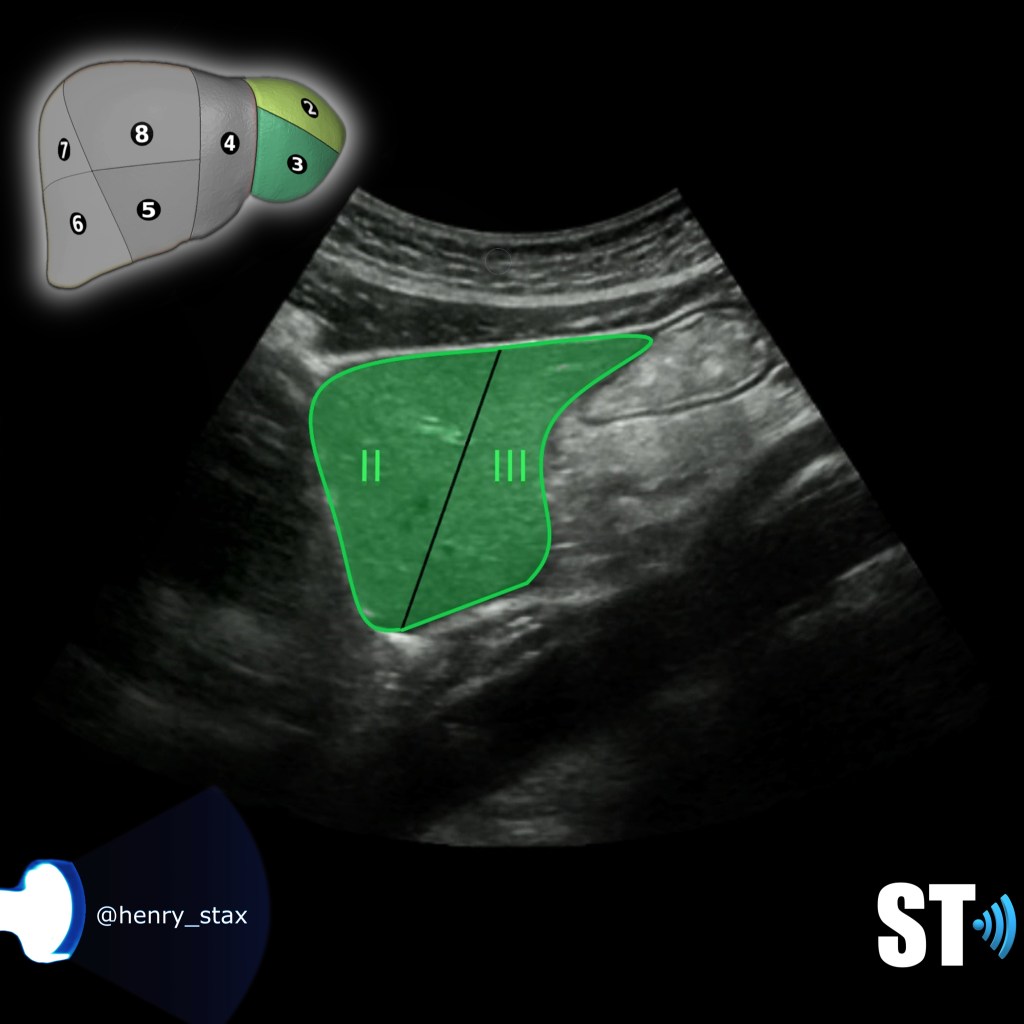

Sagittal

Liver Lt Lobe

Liver Left Lobe segments II and III

Segment II and III is the superior and inferior lateral left lobe.